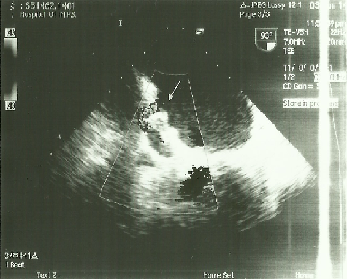

Материал и методы: с 2013 по 2015г. в Центральной клинической больнице №2 им Н.А. Семашко ОАО «РЖД», было имплантировано 15 окклюдеров «WATCHMAN» пациентам с персистирующей формой фибрилляции предсердий неревматической этиологии, поступившим для выполнения электроимпульсной терапии, электрофизиологического исследования и радиочастотной аблации, имплантации электрокардиостимулятора. Показаниями к эндоваскулярному вмешательству были угроза повторных тромбоэмболий, высокий риск кровотечений, наличие тяжелой сопутствующей соматической патологии, неэффективность консервативной антикоагулянтной терапии. Из исследования исключались пациенты со стенозом левого атриовентрикулярного отверстия, тромбами в ушке левого предсердия. На дооперационном этапе всем пациентам выполнялась стандартная трансторакальная эхокардиография и чреспищеводная эхокардиография, для оценки анатомии ушка левого предсердия, определения его размеров в четырех проекциях, а также взаимоотношение ушка левого предсердия и левой верхней легочной вены. Для оценки риска инсульта и тромбоэмболических событий использовалась шкала CHA2DS2 и ее новая модификация CHA2DS2-VASc. Перед выпиской из стационара всем оперированным больным проводилась контрольная чреспищеводная эхокардиография, которую повторяли в послеоперационном периоде через 1.5, 6 и 12 месяцев.

Результаты: средний возраст больных составил 52 года. Всем пациентам процедура имплантации окклюдера «WATCHMAN» проведена успешно. Вмешательства выполнялись без использования общего наркоза, под местной анестезией. Средняя продолжительность операции составила 42±11,3мин. На каждого пациента было использовано по одному устройству. Смены окклюдера в связи с неверным определением размера или другими причинами не было. У 5 пациентов (анатомическая форма ушка «chicken wing») под углами 90 — 135° интраоперационно выявлена протрузия нижнего края окклюдера до 1/3 длины. У пациентов с имплантированным в УЛП окклюдерами 33 и 27 размерами, по нижнему краю регистрировался резидуальный поток диаметром 5мм и 2 мм соответственно. Осложнений во время операции, так и в ближайшем послеоперационном периоде не зарегистрировано. Через 12 месяцев наблюдения изменений положения окклюдера и наличие тромбов на поверхности окклюдера и в УЛП ни у одного пациента не зарегистрировано. Не отмечено дислокации, эмболизации, изменения положения устройств. Диаметр резидуального потока по нижнему краю импланта 33 размера у одного пациента через 6 месяцев уменьшился с 5 мм до 2 мм, у другого остался прежним – 2 мм. Ни у одного пациента не были зафиксированы эпизоды нарушения мозгового кровообращения, а также другие тромбоэмболические события.